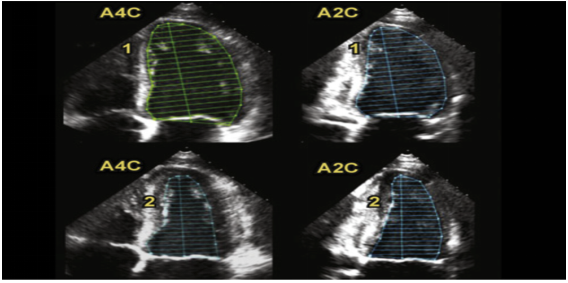

(1)左心射血分数(LVEF):最常用的一个值,通常采用心尖双平面改良Simpson法图21或者Teichholtz法(图22)测量。若有心肌节段运动异常,推荐Simpson法,在心尖四腔心切面或心尖两腔心平面,利用超声系统自带的软件,描记左心室在收缩末期和舒张末期的边界,设备自动算出LVEF值。若无心肌节段运动异常,可采用M超胸骨旁长轴切面Teichholtz法来测量,取样线垂直于室间隔和左室后壁。Teichholtz法的LVEF计算公式为:

各种方法测量的LVEF参考值通常大于50%。

图片

图21. Simpson法在A4C切面或A2C切面测量LVEF